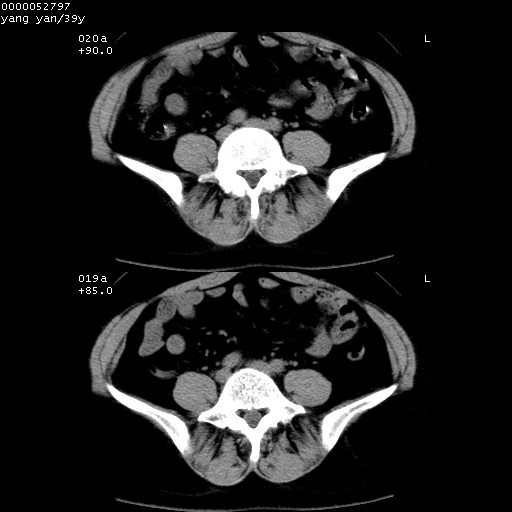

患者 女,39岁。因外伤检查,偶然发现。

典型!双侧骶髂关节致密性骨炎。

典型!病变主要累及双侧髂骨。常见于育龄期妇女。

致密性骨炎,一般不跨越关节面,可是这个骶骨关节面也有硬化。

髂骨致密性骨炎系一种以骨质硬化为特点的非特异性炎症,有高度致密的骨硬化现象,尤其以髂骨下2/3更为明显,但关节间隙则无改变。因位于骶髂关节,且该关节症状明显,故又称之为“骶髂关节致密性骨炎”。 本病90%以上为中年女性,以妊娠后期、尤其分娩后为多见,亦可见于尿路或女性附件慢性感染后,或盆腔内其他感染。此外,臀骶部的外伤亦可诱发或引起本病。  妊娠、分娩及外伤均可引起骶髂关节韧带的撕裂而易使局部的血供受阻。因此早期局部呈现充血、水肿及渗出增加等,渐而局部出现增生与变性反应,随着胶原纤维的致密化而向硬化演变;血管形成厚壁血管,易闭塞而引起髂骨耳状面处缺血和缺氧,骨质呈现硬化性改变,以致手术时局部出血较少。骶髂关节囊壁显示纤维增生、弹性降低及松动样改变。继发于盆腔内炎症者亦出现相类似的病理改变,可能系细菌内毒素作用所致。